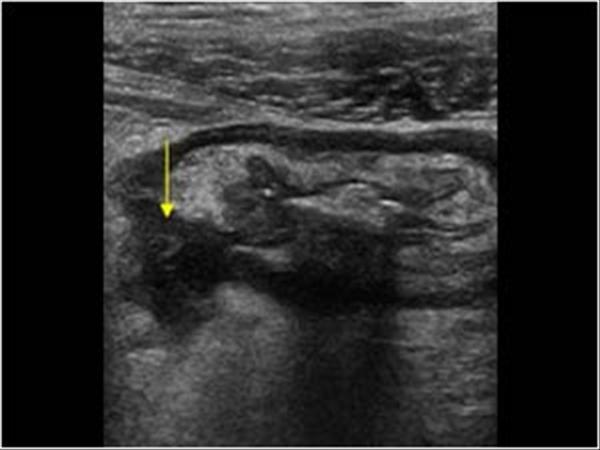

Patient recently had ERCP

pneumobilia

Air within the biliary tree